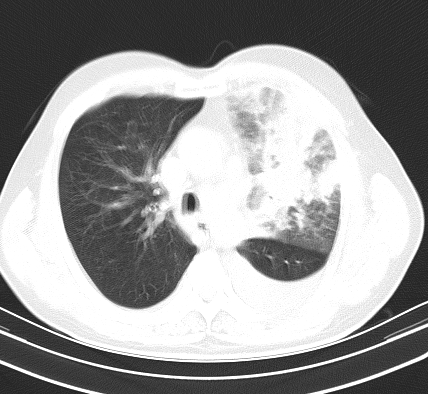

以下是引用老爱克斯新网客在2008-7-31 6:30:00的发言:[br]左肺上叶大片状病灶,左肺上叶支气管狭窄呈鼠尾状,左肺门增大,纵隔内见肿大淋巴结,左侧胸腔积液,余肺清晰。左肺中心型肺癌淋巴结转移,

以下是引用zjb在2008-7-31 6:32:00的发言:[br]左侧中心性肺癌 阻塞性肺炎 肺不张 胸腔积液 建议气管镜

以下是引用zjzjr在2008-7-31 8:45:00的发言:[br]考虑左侧中心性肺癌伴阻塞性肺炎,左肺上叶肺不张,纵隔淋巴结转移;左侧胸腔积液。建议行纤支镜检查。

以下是引用sdzyy在2008-7-31 8:47:00的发言:[br]病灶较治疗前有所进展,胸水增多, 左侧中心性肺癌 并 阻塞性肺炎 肺不张 胸腔积液 可能性大; 建议气管镜检查。 [br] [br]